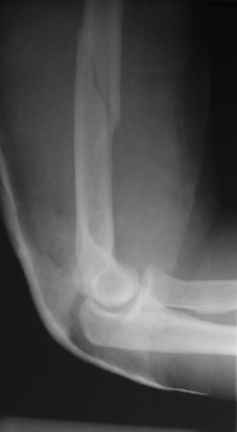

Теперь непосредственно по больному. Лечим функциональной повязкой, добились вот чего (приложение). Будем признательны за дальнейший комментарий - мое мнение, что можно продолжить без операции.